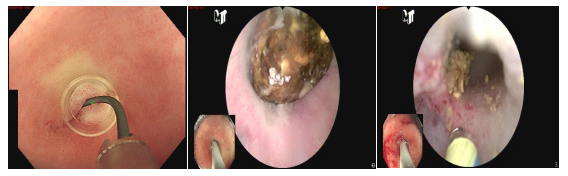

"液電碎石"巧解難題——內(nèi)鏡微創(chuàng)治愈闌尾巨大結(jié)石合并慢性闌尾炎

患者闌尾巨大結(jié)石合并慢性闌尾炎,因闌尾口嚴(yán)重粘連操作極具挑戰(zhàn)。團(tuán)隊(duì)?wèi){借嫻熟技術(shù),在導(dǎo)絲精準(zhǔn)引導(dǎo)下,成功實(shí)施內(nèi)鏡下"液電碎石",取出結(jié)石并徹底沖洗,手術(shù)一氣呵成,展現(xiàn)了內(nèi)鏡微創(chuàng)治療復(fù)雜闌尾病變的技術(shù)優(yōu)勢。